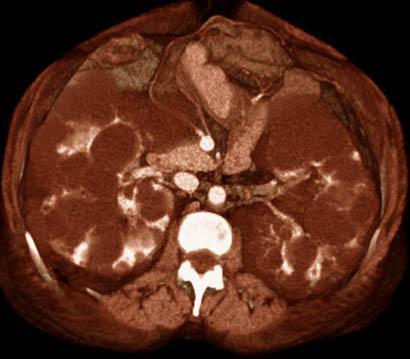

Poliquistosis renal